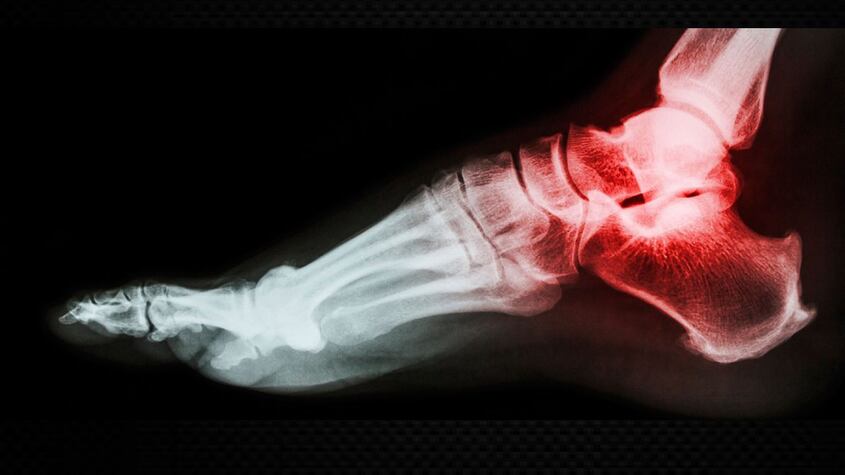

Indican que una prueba básica, como una radiografía, era esencial durante la primera asistencia para despejar cualquier duda.

Inicialmente, el juzgado determinó que “los síntomas de la actora eran perfectamente compatibles con el esguince de tobillo, por lo que no estaba indicada la radiografía en una primera asistencia”. Sin embargo, tras analizar el caso, el TSJA concluyó que “ha existido un retraso relevante en el correcto diagnóstico” de la lesión, subrayando que “hasta ocho meses después del traumatismo no se establece el diagnóstico de fractura”.

El TSJA argumenta que, aunque inicialmente es posible confundir un esguince con una fractura, “no cabe duda de que para salir de la duda, la realización de una prueba básica como la radiografía es elemental”. Esta prueba es sencilla, no requiere autorización especial en el sistema sanitario y no está contraindicada en pacientes como la apelante.

El tribunal destaca que “para descartar la fractura, dada la probable confusión con el esguince”, la radiografía “está indicada”. Además, señala que el sistema sanitario no puso a disposición de la paciente todos los medios necesarios para establecer el mejor diagnóstico posible, considerando que “existe un error de diagnóstico inicial, que no precisa la afirmación de ninguna actuación culpable, que en principio debe generar responsabilidad”.